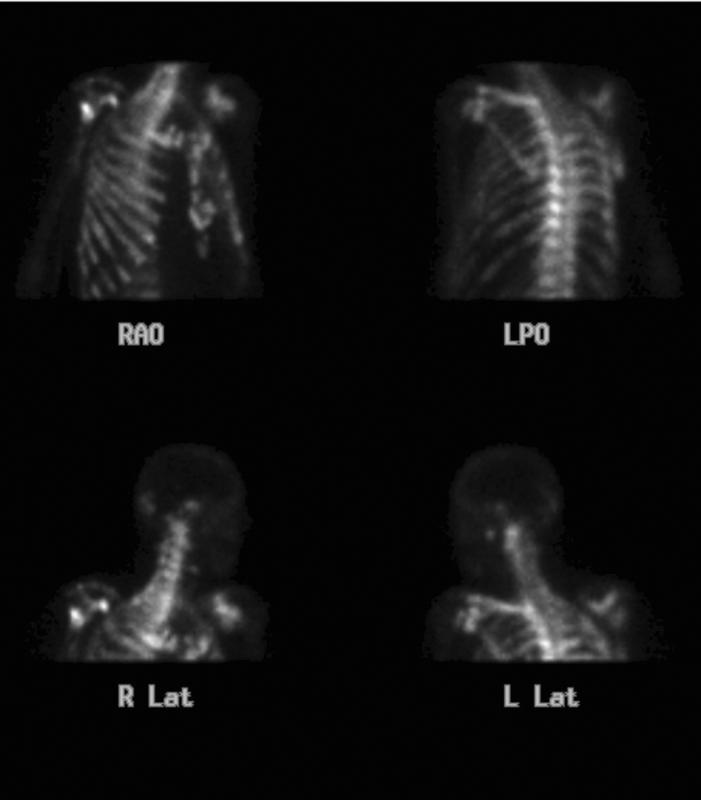

Gallery Lung Cancer Mets Prostate Bone scan

Prostate Bone scan